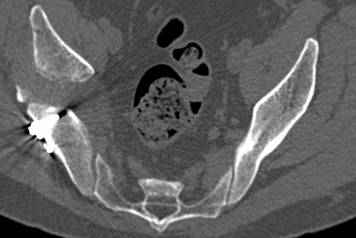

Интересно было бы посмотреть рентгенограммы до операции. У меня впечатление, что я не все вижу, что тут есть... Уважаемые Господа "тазисты" и "тазологи", к какому типу переломов вертлужной впадины по Летурнелю вы бы отнесли это случай?

Из переломов проходящих через крыло и/или заднюю стенку ни простой перелом "передней колонны" (явно имеется пером задней стенки, и не видно перелома седалищной или лонной), ни простой "поперечный", ни ассоциированный "Т-образный" (т.к есть перелом крыла и не видно перелома седалишной), ни ассоциированный "задняя колонна+задняя стенка", на ассоциированный "поперечный+задняя стенка", ни ассоциированный "передняя колонна+задняя гемисфера" (не видно перелома седалищной), ни ассоциированный "обе колонны" (не видно перелома лонной седалищной) не подходят под эту классификацию....

к таковым себя не причисляю, но...обычное дело для нашей страны - выкладывать 3D и не показывать стандартные проекции Judet. Дигност представляет те ракурсы, которые по-его мнению наиболее информативны, более того комп сам достраивает какие-то мелкие повреждения по 3D по своему усмотрению. По данной реконструкции можно предполагать высокий двухколонный перелом с оскольчатыми передней и задней колоннами, оскольчатую высокую переднюю колонну с задним полупоперечником или одно из перечисленных с вовлечение КПС. У меня впечатление за второй вариант, но нужно обследовать нормально - проекции, сканы.

высылаю дополнительно сканы.